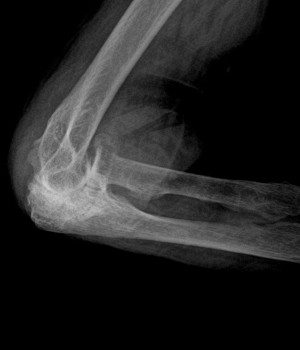

End-Stage Osteoarthritis of the Elbow